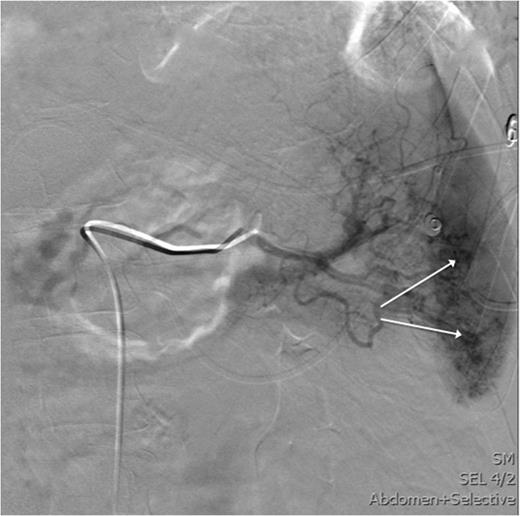

After the CT study, angiographic embolization of the splenic artery was performed. Angiographic catheter was inserted through the right femoral artery and guided into the splenic artery through the celiac trunk. The Spongostan (Ethicon Inc., Somerville, NJ, USA) particles were deployed to the branches of the splenic artery as the contrast leakage was seen in multiple locations. The proximal SAE with three Gianturco coils (Cook Medical Inc., Bloomington, IN, USA) and one Azur Peripheral HydroCoil (Terumo Medical Corporation, Somerset, NJ, USA) were deployed 4 cm distal to the celiac trunk (Figs 3 and 4). After the procedure, the patient was admitted to intensive care unit.

This image shows an angiography of the splenic artery observing splenic contrast leak (white arrows).

Angiographic imaging post-embolization observing four proximal coils in the splenic artery 3–4 cm distal to the celiac trunk.